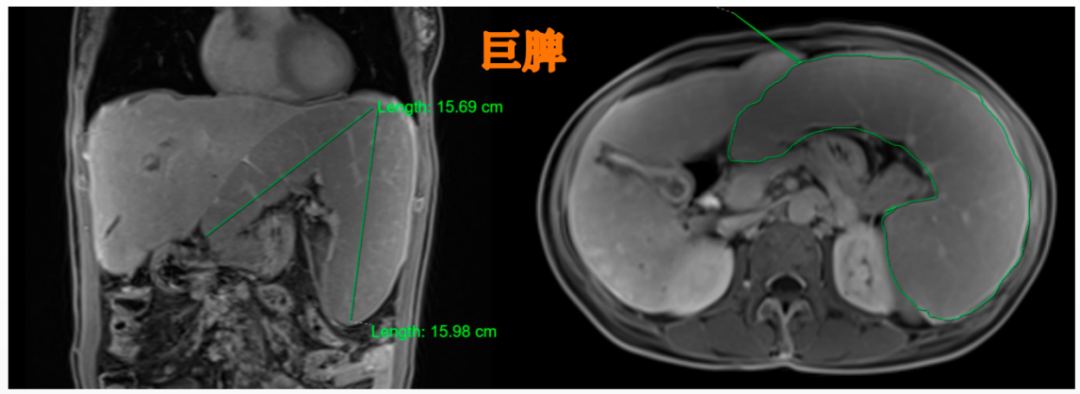

腹部增大没当回事,竟引来脾大,脾亢,消化道出血.